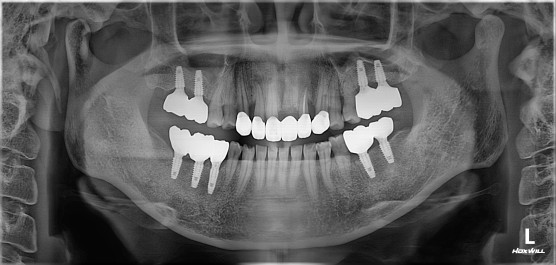

치료명 : 신경치료 및 지르코니아관 수복, 임플란트

c.c 상악 전치부 상담 원하심. 치아 사이 벌어져 있음

#21.22 정출, #21발치 설명드림. #131211X2223 브릿지 진행